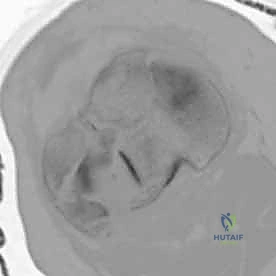

3. الأشعة المقطعية المحوسبة (CT Scan) - المعيار الذهبي

لا يمكن إجراء جراحة لكسر ثنائي اللقمة دون إجراء أشعة مقطعية (يفضل مع إعادة بناء ثلاثية الأبعاد 3D).

* توفر الأشعة المقطعية خريطة دقيقة لكل شظية عظمية.

* تحدد مقدار الانخساف في السطح المفصلي بالمليمتر.

* تكشف الشظايا المخفية، خاصة في الجزء الخلفي من الركبة (Posterior Coronally oriented fragments) والتي تتطلب خطة جراحية خاصة لتثبيتها.